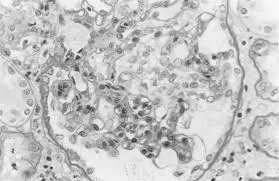

A DRPAD não é contraindicação à DP — e, na prática, muitos pacientes têm resultados comparáveis à hemodiálise. O “porém” está na mecânica: rins/hepatomegalia podem reduzir tolerância a volumes, aumentar risco de hérnias e extravasamentos, e piorar desconforto respiratório. Com técnica adequada (cateter presternal ou lateral, volumes menores, cicladora noturna e decúbito supino), a maioria das barreiras é contornável. Neste post, revisamos quando a DP é ótima, quando exigir cautela e como ajustar a prescrição para segurança e qualidade de vida.